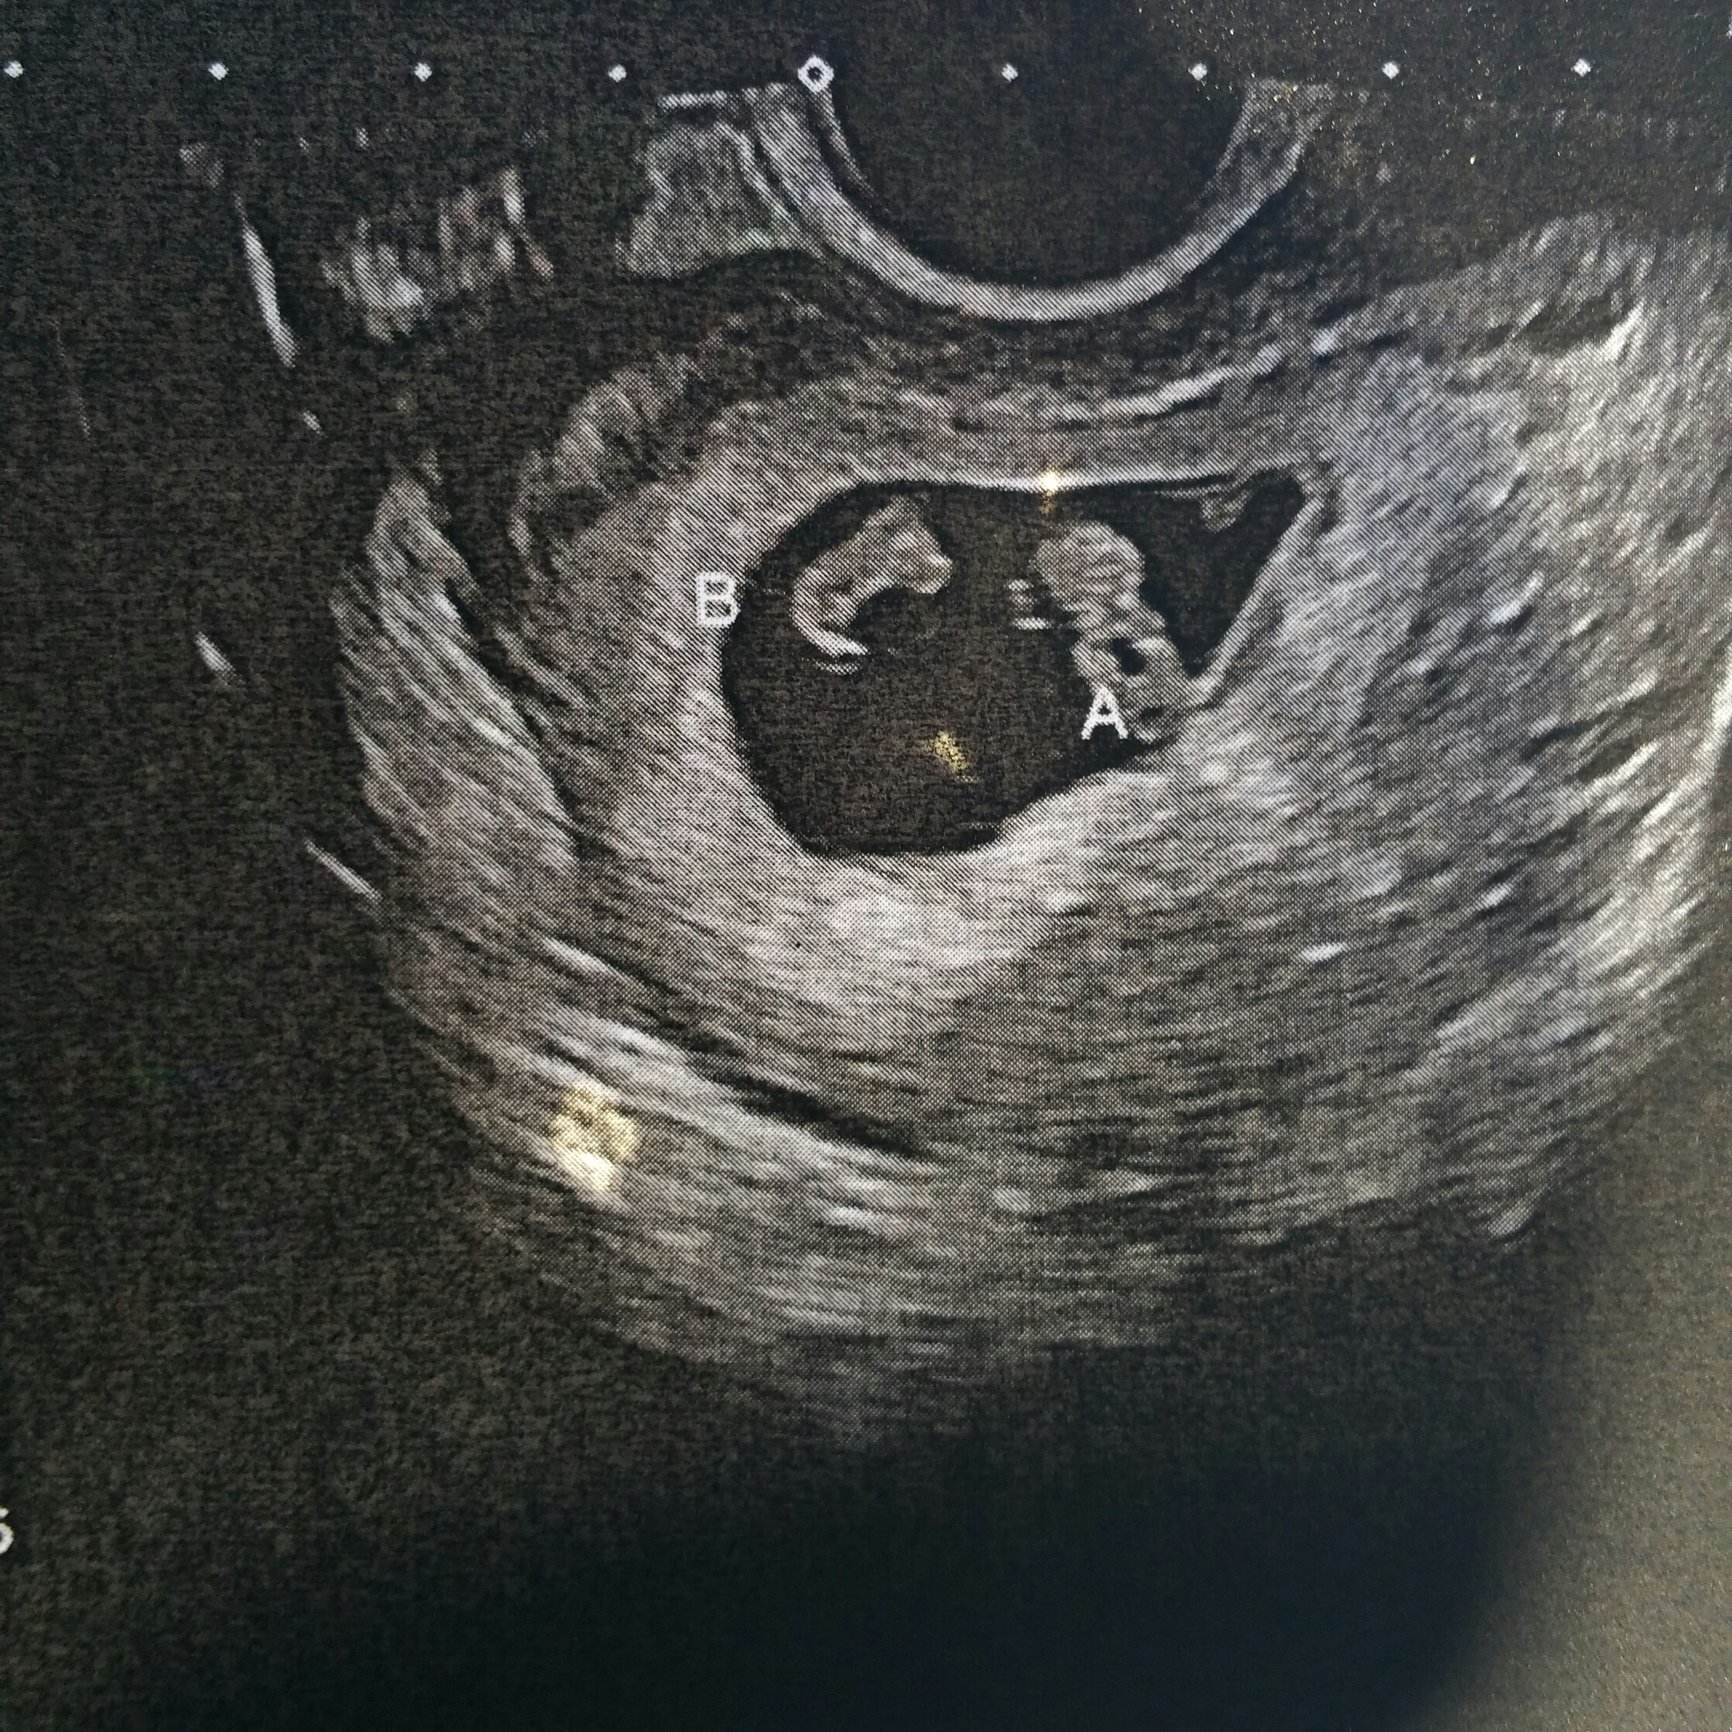

Hm well the ultrasound technician worried me by saying they may share an amniotic sac and said i needed another ultrasound to confirm but havent even talked to a dr and its been 2 weeks. Cant get in to an ob yet and its driving me nuts.

@notaknottie912 Congrats on your twins! Just wanted to say, I’m expecting mo/di (identical) twin girls, and my Nurse practitioner told me the same thing at first - that they may share an amniotic sac. Just to put your mind at ease, they say that to everyone, so I wouldn’t worry yet until you get confirmation. I did, and it drove me insane. The chances of you having mo/mo twins (that share an amniotic sac) are SUUUUUPER SLIM. They’re very rare. Usually, the machines they use in the first ultrasound aren’t very high tech, so theyll

probably schedule another appt for you to see if you have a separating membrane.

Call me crazy, but I kind of think I see a sac around twin b at the very least. You’ve probably got some mo/di’s mama!

Twins - Identical mo/mo

Mo/mo twins, as your all saying, are quite rare and very high risk. I’m keeping myself calm and relaxed about it. I get more appointments for ultrasounds which has been great. So far, 10 weeks in, Ive already had 4.